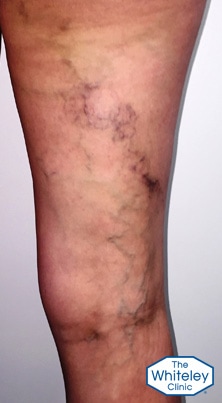

As can be seen by the pictures, the legs look relatively normal when viewed from the front. However there are two very brown areas on the outside of the left calf, with a very dark brown stain on the left calf muscle at the back.

There is a very impressive varicose vein with thread veins and brown stains, snaking diagonally across her right thigh at the back from the area of the vulva to the outside of the knee.

Finally, checking sides of her thighs at the very top, she had very clear varicose veins in the para-vulval region on both sides, which are easier to see on the left.

This lady has thread veins (telangiectasia) which means she is at least a C1. She also has varicose veins, raising her grading to C2. However because she has had recurrent phlebitis, which has resulted in skin damage, she is graded as C4.